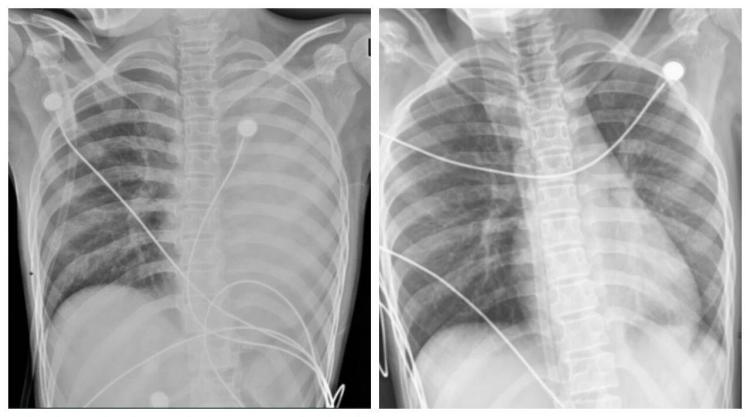

△笑笑治疗前,左肺呈“白肺”状态,治疗后“白肺”被吸收,心脏边缘清晰可见。图源:浙大四院

一开始,她只是轻微咳嗽,发热后在外院检查提示肺炎、肺不张,转诊到浙大四院儿科时,笑笑出现呼吸急促、胸闷胸痛,血氧饱和度勉强维持在90%左右,胸片显示左肺已完全呈“白肺”改变,病情急剧恶化。

术后第二天,笑笑呼吸困难、胸痛的症状明显好转,病情得到了初步控制。经过精准抗感染、祛痰、抗炎等系列治疗,笑笑逐渐康复,顺利出院。